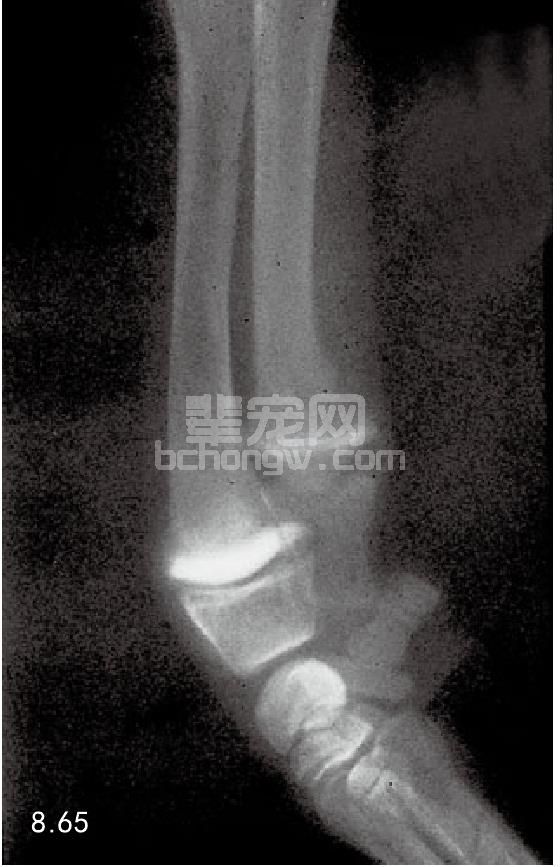

诊断 X线片显示高密度硬化的“锤条”,可以在未成熟犬的长骨的干骺端看到(图8.65)。多数发生在尺 骨和桡骨的远端。慢性维生素D、磷、铋中毒都会显示类似的影像学病变。

图8.65 未成熟犬的干骺端“锤条”。